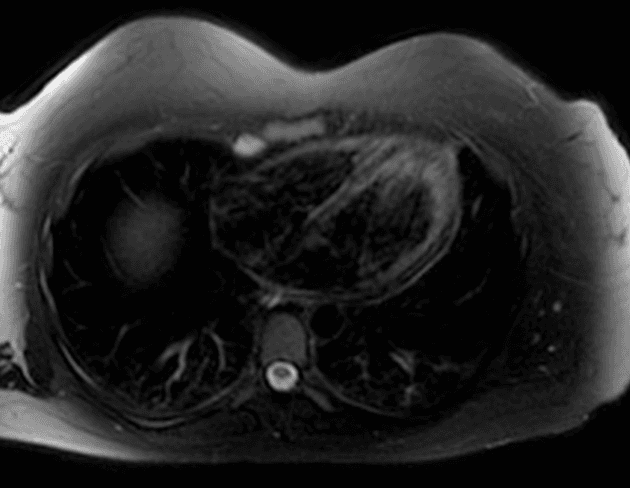

Axial T2

- Gan to với tín hiệu phù quanh cửa (periportal edema signal).

- Dày thành túi mật (mural thickening) và phù thành túi mật lan tỏa.

- Dịch ổ bụng (ascites) mức độ nhẹ.

Trong trường hợp vàng da, chụp cộng hưởng từ đường mật tụy (MRCP) có thể được sử dụng để đánh giá sỏi đường mật. Tuy nhiên, trong nhiều trường hợp, nguyên nhân do viêm gan virus cấp tính (vi rút viêm gan A). Các hình ảnh học thường gặp bao gồm gan to (hepatomegaly) với tín hiệu phù quanh cửa trên hình cộng hưởng từ trọng T2 (T2 WI). Dày thành túi mật lan tỏa và phù thành túi mật cũng là những dấu hiệu điển hình.

- "Phù quanh cửa trên cộng hưởng từ trọng T2 là dấu hiệu hình ảnh quan trọng của viêm gan cấp."

- "Dày thành túi mật lan tỏa có thể xảy ra trong các bệnh lý toàn thân như viêm gan virus cấp, không chỉ trong viêm túi mật."

Viêm gan cấp, đặc biệt do virus viêm gan A, là nguyên nhân phổ biến gây vàng da và đau bụng ở các vùng lưu hành. Chẩn đoán hình ảnh đóng vai trò hỗ trợ, với cộng hưởng từ cho thấy gan to, phù quanh cửa (tín hiệu tăng trên hình trọng T2) và dày thành túi mật lan tỏa do viêm toàn thân và ứ trệ tĩnh mạch. Mặc dù MRCP thường được thực hiện để loại trừ tắc nghẽn đường mật, việc không thấy giãn ống mật hay tổn thương cản quang giúp khẳng định nguyên nhân không do tắc nghẽn. Xác nhận chẩn đoán bằng xét nghiệm men gan tăng và IgM kháng HAV hoặc PCR dương tính là cần thiết. Chẩn đoán hình ảnh giúp phân biệt viêm gan cấp với các nguyên nhân khác gây vàng da như sỏi ống mật chủ, khối u hoặc bệnh lý đường mật nguyên phát.